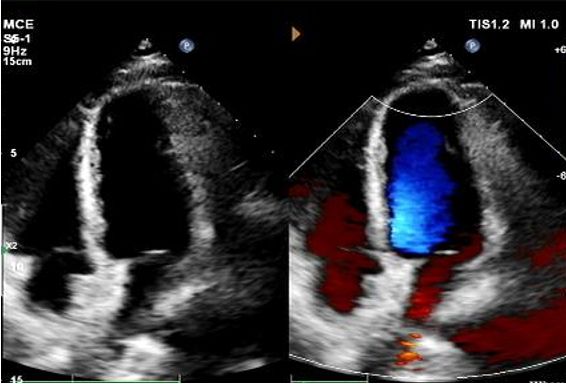

Jour 1 à 9 mois:

Aucun shunt résiduel n'a été observé.

Réduction progressive de l'échogénicité du dispositif.